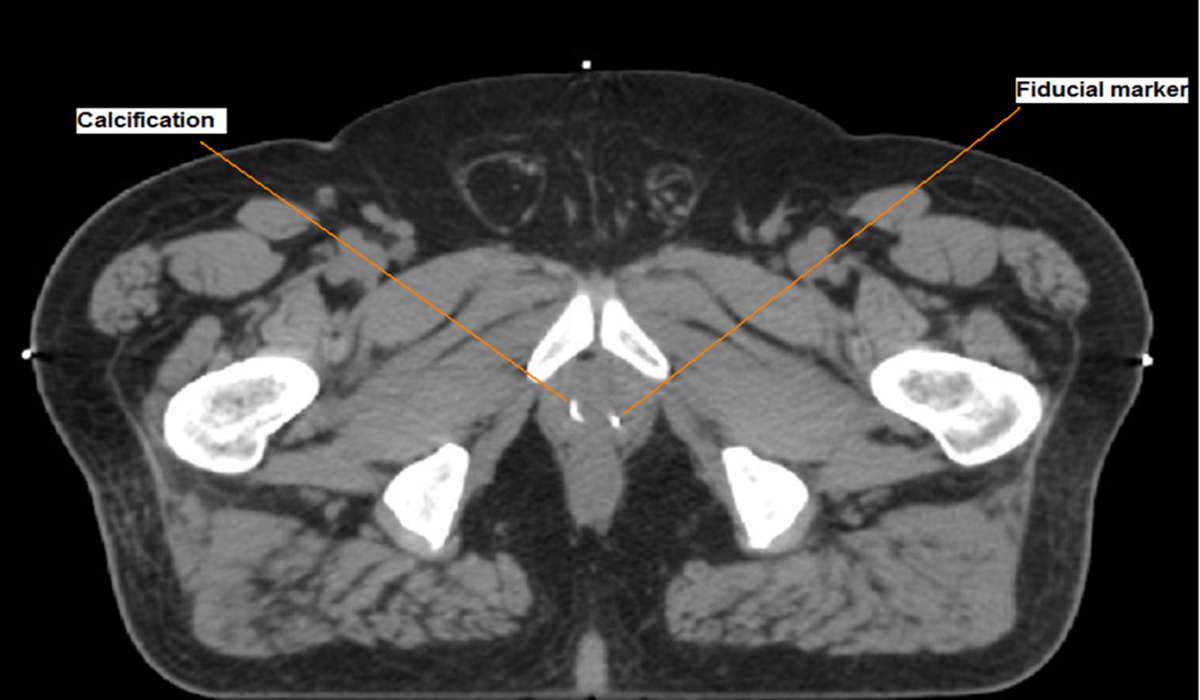

Radiotherapy is an effective treatment for prostate cancer and so many men receive radiotherapy as part of their treatment. For the radiotherapy to be most effective it is important that the doctor knows the precise position of the prostate during the treatment. A standard approach to ensuring this is to insert “markers” into the prostate which can then be seen during treatment so that the radiotherapy treats exactly the correct area. Unfortunately the surgery needed to place these markers can sometimes cause pain, bleeding and infection.

Angela’s research study will look at whether it is possible to use different images of the prostate, which show naturally occurring changes, to precisely locate the prostate and use this to plan the treatment. If this works it will benefit patients by reducing the need for a surgical procedure while ensuring maximum treatment accuracy.

FIG 1. Image of the prostate showing surgically implanted marker and naturally occurring calcifications. The research aims to use a clinical trial to determine if the naturally occurring calcifications in the prostate can be used to effectively guide radiotherapy treatment and if this could be introduced into clinical practice.